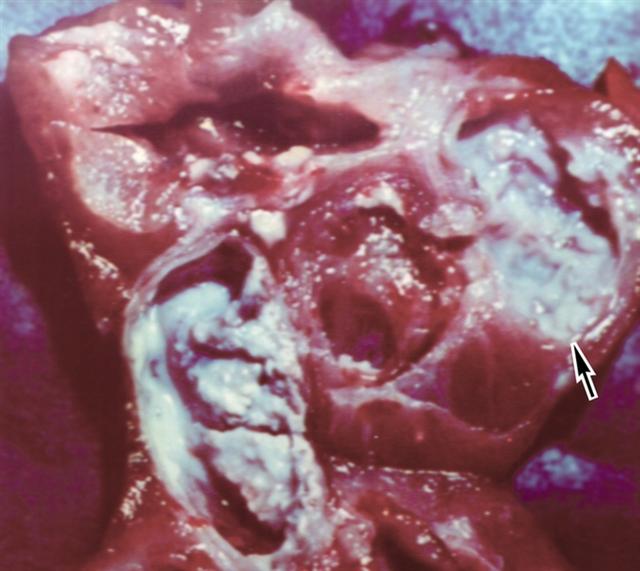

Рис. 8б. Операционный препарат верхнего сегмента правой почки на разрезе при кавернозном туберкулезе почки: видны крупные каверны (указаны стрелкой), заполненные казеозно-гнойными массами.